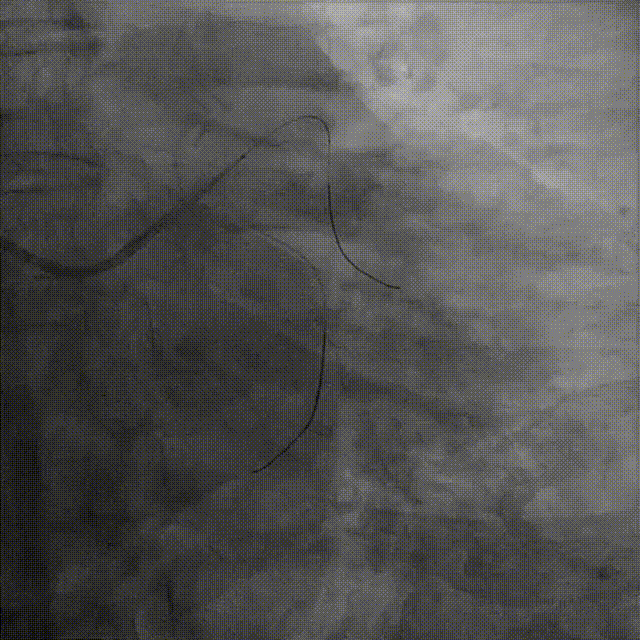

介入经过——最后影像

7,给与4.0x15mm非顺应性球囊进行高压后扩张,压力维持在16~20atm。最后检查血管影像。